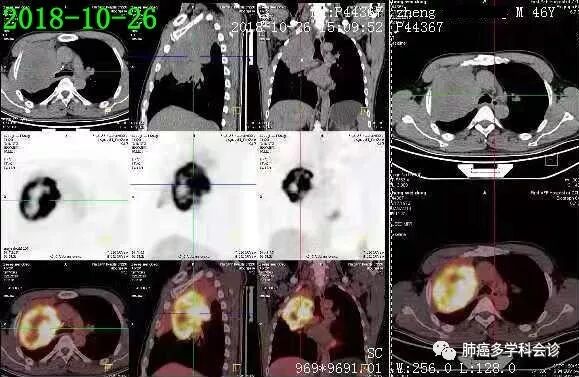

PET-CT示(2018-10-28):右肺上叶近肺门软组织肿块代谢不均匀活跃,远侧肺组织不张;右侧锁骨上/下及纵隔(2R)和4L 小淋巴结淋巴结代谢稍活跃。

- 【多学科会诊病例】 以下为一位肺鳞癌患者经过二个方案化疗后,疾病进展、不耐受继续化疗。三线“PD-1抗体+安罗替尼”治疗, 2周期后肿瘤明显缩小: 患者郑WD,男,46岁,吸烟20余年,平均20支/